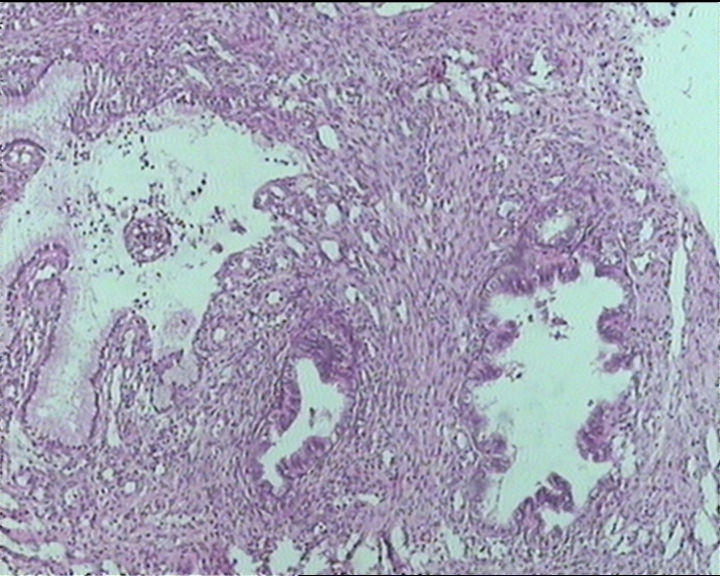

54岁女性,临床“宫颈息肉”送检;巨检:组织一块1。5*1CM,灰红。

Sternberg病理学上诊断宫颈原位腺癌的标准是腺体的上皮去粘液分化,呈乳头状或筛网状增生,核分裂易见,这例显然达不到此标准。此例还是归入到腺上皮不典型增生为好。

It is benign. Benign endocervical polyp with tubal metaplasia.

输卵管粘膜化生

细胞及腺体均有异形,图6、11、16象有纤维间质反应,考虑高级别上皮内瘤变/原位癌,腺癌不能除外。